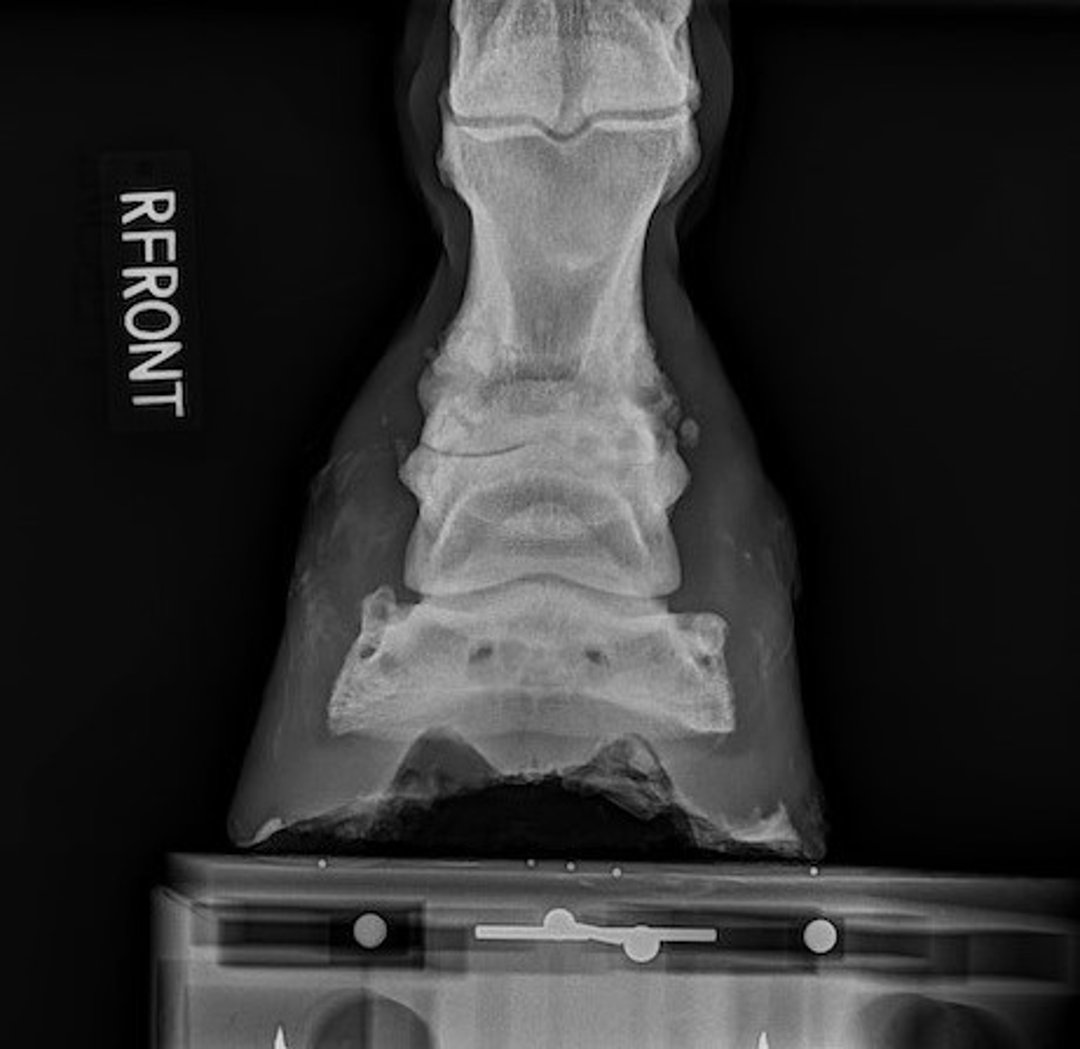

Pastern osteoarthritis (ringbone), radiograph, horse

Radiograph showing severe osteoarthritis of the proximal interphalangeal joint in a horse. Note the loss of joint space, new bone formation (ringbone), and subchondral lysis.

Courtesy of Dr. Stephen Adams.